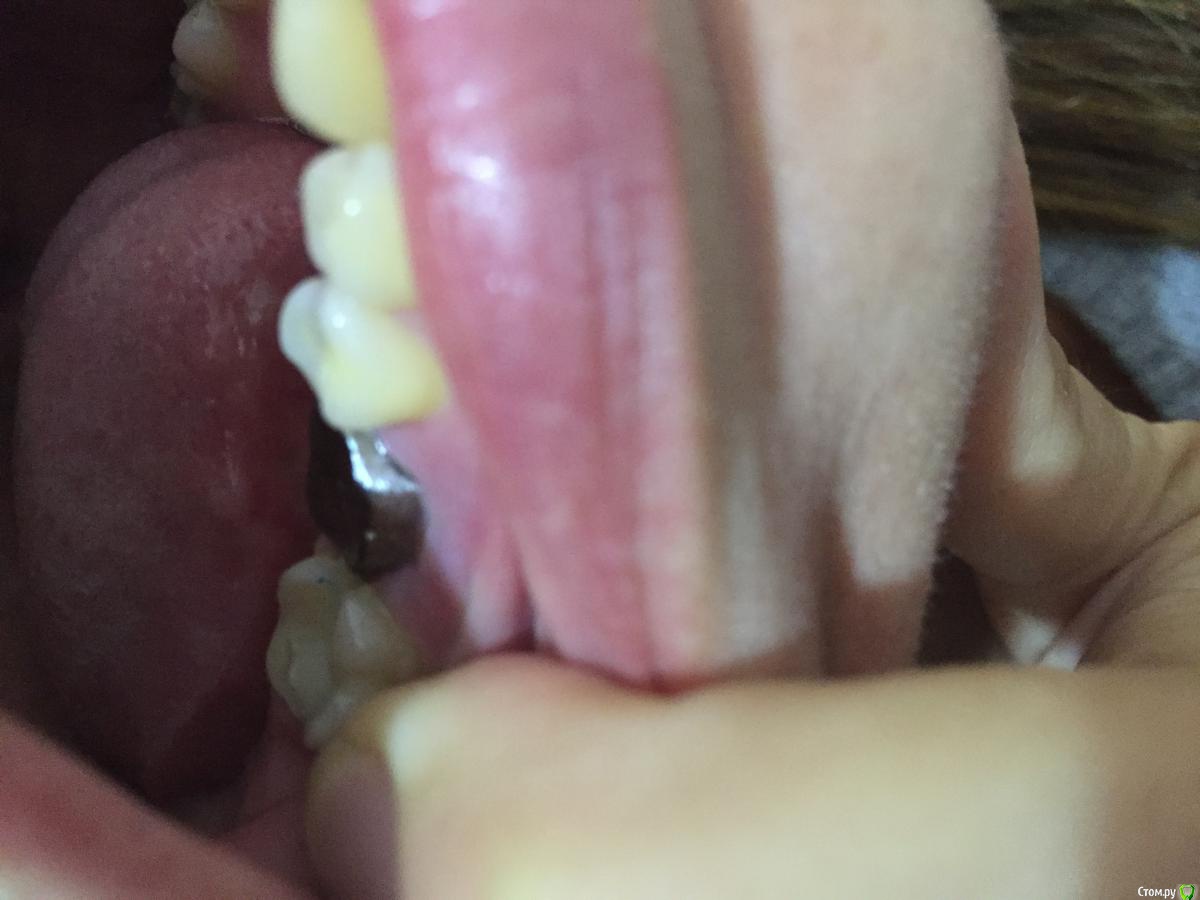

Мария Сп Опубликовано 28 сентября, 2018 Поделиться Опубликовано 28 сентября, 2018 (изменено) Здравствуйте, уважаемые доктора!Просьба помочь. Зуб треснул, доктор сказал нужно устанавливать металлокерамическую коронку. Взяли слепок. Через 2 недели установили культю, т.к. от зуба остался только корень и металлическую основу под керамическую коронку (заранее извиняюсь, не знаю как правильно называется металлическая основа).После установки данной металлической основы доктор сказал, что у меня зуб широкий и плоский и, что вероятнее всего керамика не покроет весь металл и будет видно металл с внутренней стороны и верхней (жевательной), т.к. осталось слишком мало места между нижней коронкой и верхним зубом. Металлическую основу доктор подточил на сколько мог, сказал, что больше не может. Также стал точить верхний зуб, но мне стало больно. Подскажите, пжл, неужели действительно в моем случае нужно, чтобы металлическая основа была настолько высокой, что нет места керамике?Можно ли это было предусмотреть и предупредить меня еще до изготовления культи и металлической основы?Можно ли переделать данную конструкцию, предполагаю, что данная металлическая основа вылита изначально сильно большой?Также доктор не устанавливал временную коронку, только металлическую основу, сделал слепок и через 2 недели ставить керамическую коронку?И могу ли я, если меня не устроит результат - сильно будет виден металл, попросить переделывать всю коронку не доплачивая?Фото прилагаю.Заранее спасибо. Изменено 28 сентября, 2018 пользователем Мария Сп Ссылка на комментарий

Мария Сп Опубликовано 30 сентября, 2018 Автор Поделиться Опубликовано 30 сентября, 2018 Фото с сомкнутыми зубами направляю. Ссылка на комментарий